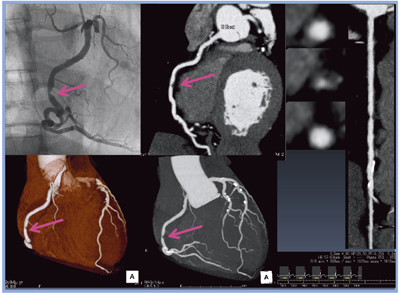

当院では,2011年3月に,80列CT「Aquilion PRIME」を導入。以後,心大血管領域のCT検査は,すべてAquilion PRIMEで行っている。臨床の一例を(図1)に示す。

図1 労作性狭心症 RCA #2狭窄